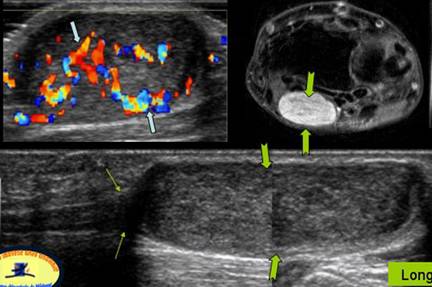

SVANOM DE NERV MEDIAN

Tumefactie dureroasa a fetei palmare a pumnului

Leziuni tisulare→ hipervascularizate → in Doppler color, placate pe n.median

Corespondenta pe IRM